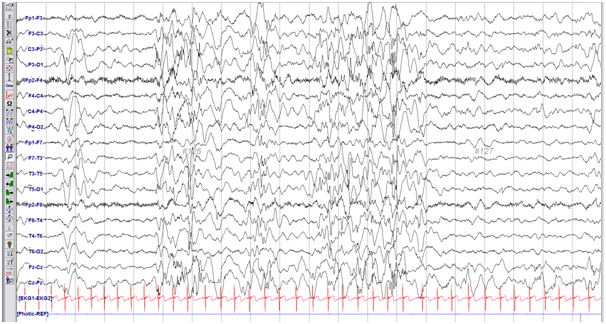

오랜만에 성장일기를 써보네요 ㅎㅎ 몇달간 매일 간헐적 경련이 일어나서 병원에 가볼까 고민하다가 며칠에서 일주일, 그 이상도 증상이 없었어요. 그러다 며칠간 증상이 반복되더니 결국 외래진료하러 갔더니 영상을 보다가 경련이 있는 아이인것 같다며 약을 먹어야 한다고 하더군요. 그날 병원에 가서 뇌파검사를 받고 남편이 출장중이라 바로 입원하기가 어려워 뇌파검사를 먼저 하고 아이를 병원으로 데리고 갔습니다. 수족관 티켓이 만료되기 전에 확인하기로 결정했습니다.

수면 중 EEG는 잠자는 아이를 깨워야 합니다. 그는 잠이 들었고, 깨는 것이 불편하다고 입을 삐죽 내밀었다. 그래서 나는 집에 갔다.